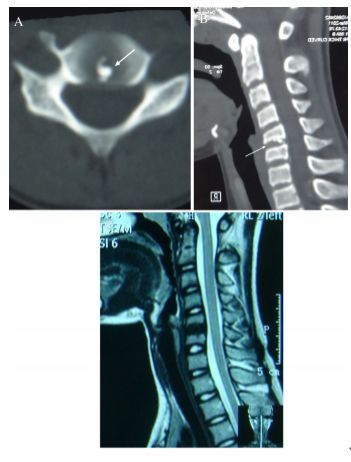

图:6岁男孩,因颈痛就诊

图:保守治疗1个月后,症状消失。19个月随访情况

图:9年后随访情况

图:11岁女孩,因颈痛3月,加重半月就诊

图:经卧床休息、非甾体抗炎药、牵引2周和颈托固定2周后症状完全缓解。2月后复查情况

图:6个月复查情况参考文献:1. World Neurosurg. (2019) 129:181-185.2. Pediatric Neurology 61 (2016) e115-e1163. BMC Musculoskeletal Disorders (2018)19:3164. Childs Nerv Syst (2016) 32:381-3865. J Spinal Disord Tech 2012;25:59-636. 中华外科杂志,1996;34(4):197-200